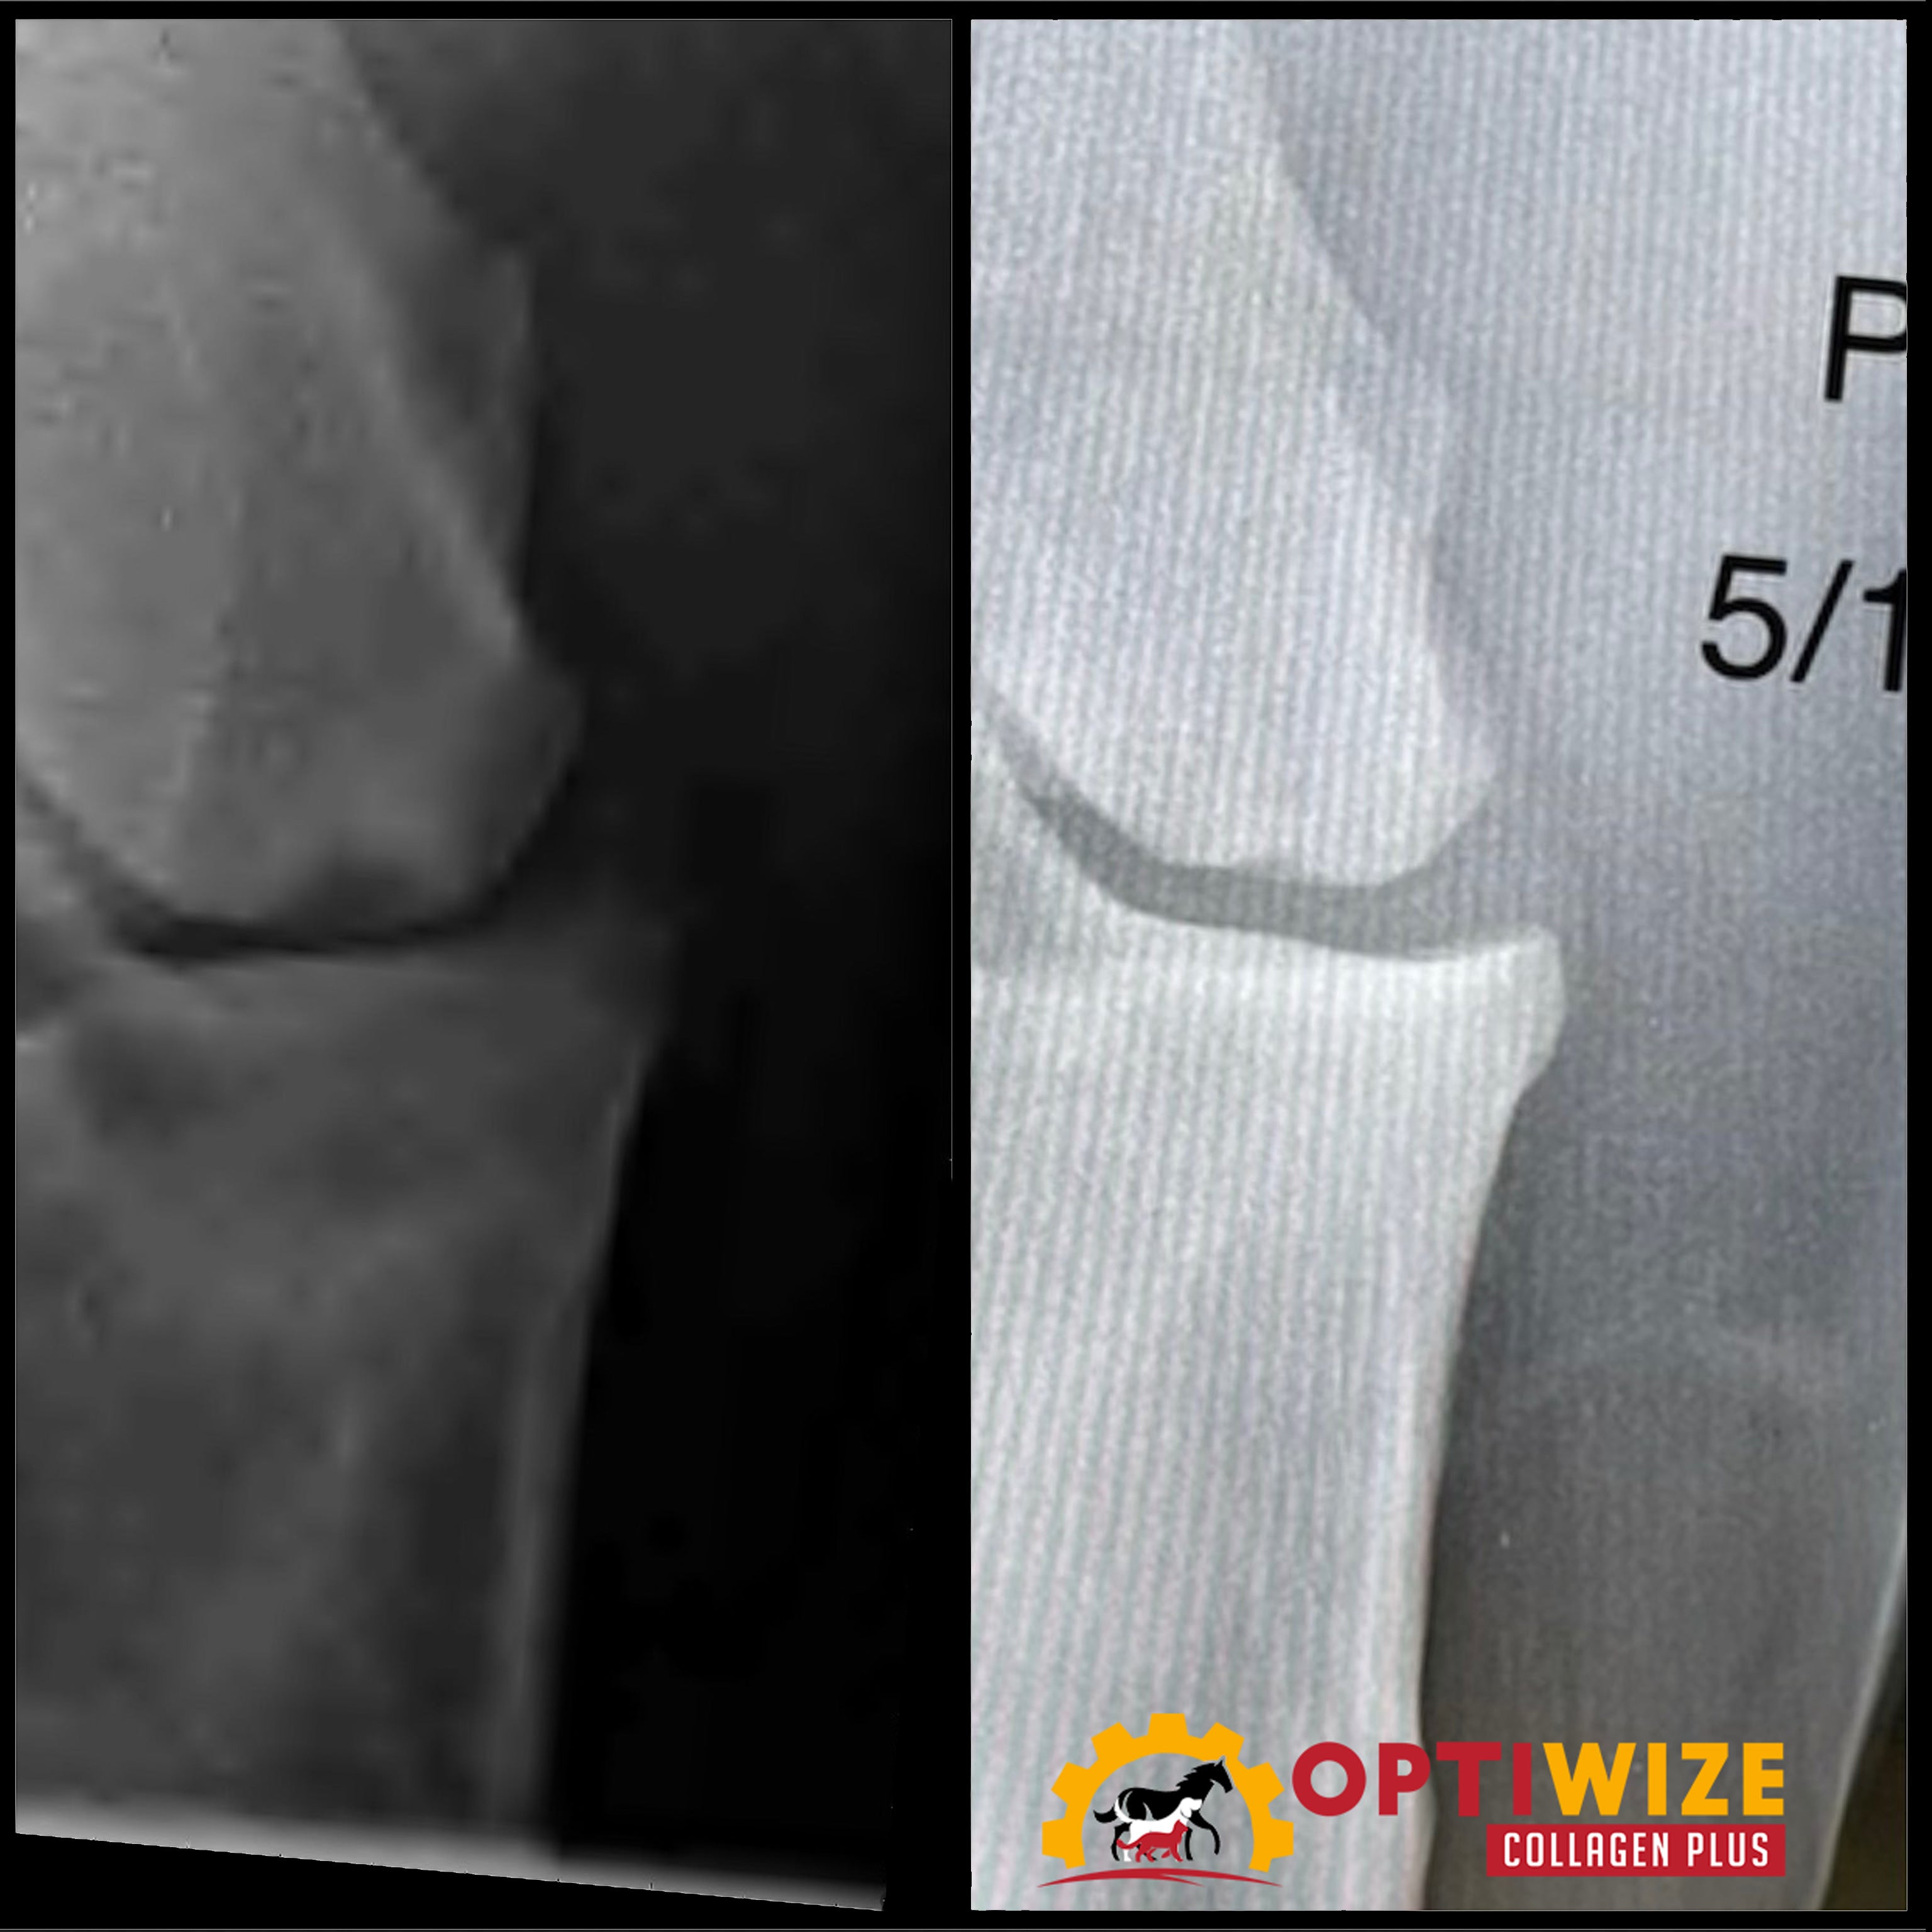

• Arthritis in horses, knee arthritis, arthritis supplement for horses

• Joint supplement horses, cartilage supplement, equine collagen supplement